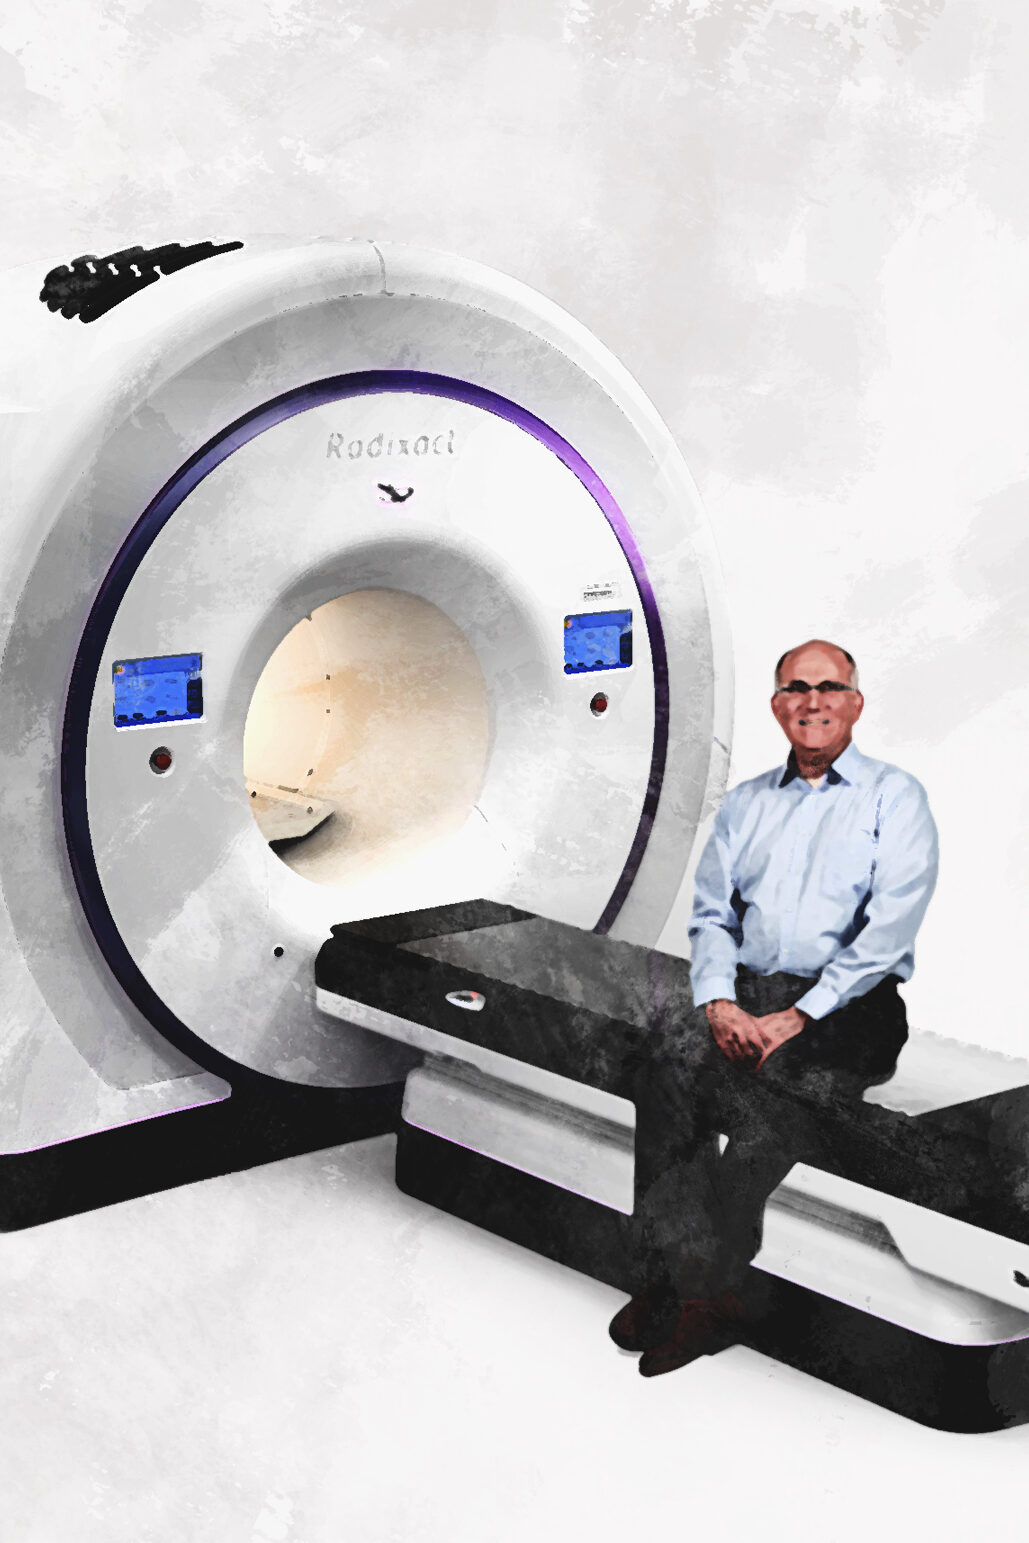

En 2001 comenzó a funcionar la Clínica de Radioterapia La Asunción y en 2003 la Unidad de Hemodinamia. Este mismo año se adquiere la primera cámara hiperbárica y en 2004 la primera resonancia magnética de magneto abierto del país.

En 2007 se realizó la primera cirugía estereotáxica. En 2008 se remodeló Emergencia para cubrir el número creciente de pacientes y en 2009 se realizó la primera diálisis peritoneal en Guatemala.

En 2022 se estableció la Unidad de Neurología, próxima a acreditarse internacionalmente para el tratamiento de los accidentes cerebro vasculares a través del Código Ictus.